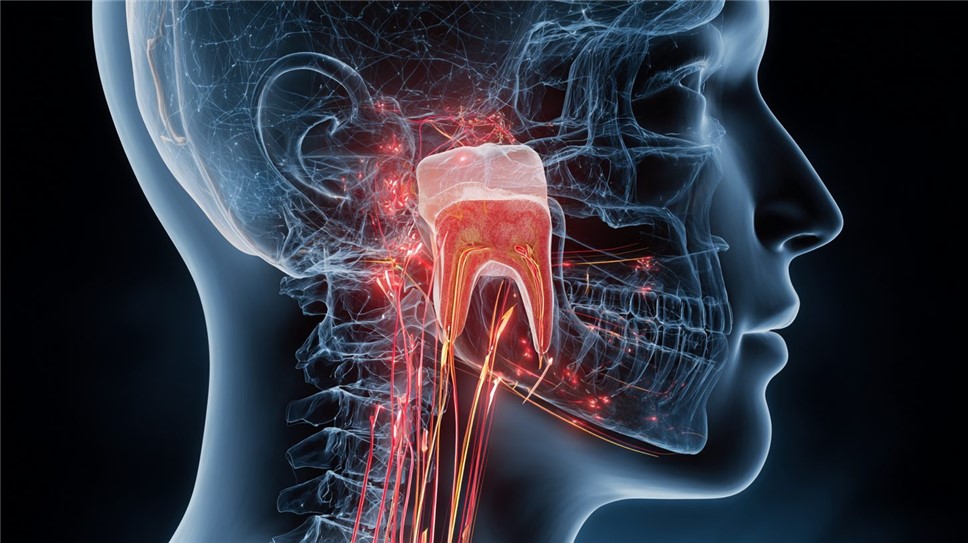

При хроническом пульпите боль становится тупой и ноющей, возникая спонтанно или при надавливании, и может иррадиировать в ухо или челюсть. Ограничением самостоятельной оценки является субъективность ощущений: гипотеза о пульпите требует подтверждения рентгеновским снимком для оценки распространения инфекции. В Санкт-Петербурге, согласно нормам Сан Пи Н 2.1.3.2630-10, клиники используют цифровую радиографию для точной визуализации.

Пульпит может выходить за рамки локальных изменений, вызывая общие реакции организма, особенно при прогрессирующем воспалении. Эти системные признаки наблюдаются, когда инфекция распространяется в окружающие ткани или кровоток, и в российской практике они учитываются в рамках комплексной оценки по приказу Минздрава РФ № 183н от 2017 года, дополненному в 2023-м. Анализ данных из Федерального регистра стоматологических заболеваний показывает, что в 15–20% случаев острого пульпита пациенты сообщают о лихорадке и слабости, что требует дифференциации от других инфекций.

Повышение температуры тела до 37,5–38°C возникает при гнойных формах и сигнализирует о бактериемии. Исследования, проведённые в НИИ стоматологии имени А.И. Евдокимова (Москва), на основе обследования 800 пациентов в 2024 году, подтверждают, что такой симптом коррелирует с лейкоцитозом в общем анализе крови, указывая на иммунный ответ. В условиях российского климата, с его сезонными колебаниями, пациенты в Санкт-Петербурге часто связывают это с простудой, что приводит к задержке обращения и риску сепсиса.

Осложнения пульпита усиливают системные проявления, переходя в периодонтит или абсцесс. При периодонтите добавляется диффузная боль в челюсти и подвижность зуба, что наблюдается в 30% запущенных случаев по статистике Минздрава. В российских клиниках, оснащённых по стандартам Сан Пи Н, это диагностируется через электроодонтодиагностику, измеряющую витальность пульпы.

Иллюстрация возможных осложнений пульпита, включая абсцесс и периодонтит.